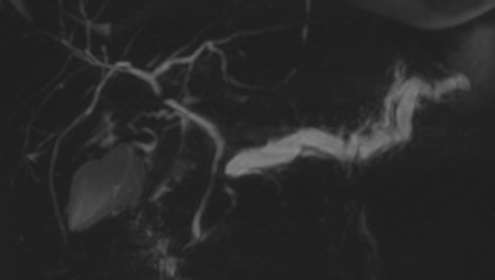

image

Lesione non visibile all’imaging. All’esame RM dilatato il dotto pancreatico principale con stop in regione istmica in assenza di visualizzazione di lesioni focali nelle sequenze precontrastografiche.

Lesione non visibile all’imaging. All’esame RM dilatato il dotto pancreatico principale con stop in regione istmica in assenza di visualizzazione di lesioni focali nelle sequenze post contrastografiche.